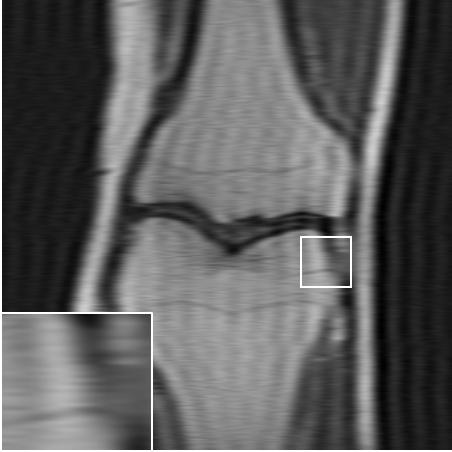

We consider the following two inverse problems: (i) Superresolution (SR), consisting of reconstructing a sharp image from measurements containing only the central low frequencies obtained by using the mask as in Fig. 2 (a & c); and (ii) Dealiasing, in which the obtained mask results in an aliasing artifact due to a coarser sampling in the phase-encoding direction. We use the masks displayed in Fig. 2(b & d). The inverse problem consists of restoring a finer sampling grid in the phase-encoding direction. Throughout the paper, we denote the experiments specifying the task name (one of the two tasks above) and the acceleration factor.

Table LABEL:tab:quant_results summarizes the results for the various experimental settings, comparing the performance of the above-mentioned benchmarks to ours. When compared to TV [6], our method achives an improvement of dB-dB in the peak-signal-to-noise ratio (PSNR). Similar results are observed for the structural-similarity measure (SSIM, about points improvement). As expected, the supervised model outperforms the proposed SSL method. However, it seems that at least for the lower distortion rates, this gap is surprisingly small. A visual inspection of the results over one slice is provided in Fig. 3. As can be observed in the zoomed-in region, our method manages to restore finer details better than the TV-based method, and even approaches the restoration levels of the supervised model in the lower distortion rates. As evident both quantitatively and visually, the TV-based method completely fails on the dealiasing task, whereas our SSL method seems to significantly alleviate the reconstruction artifacts.